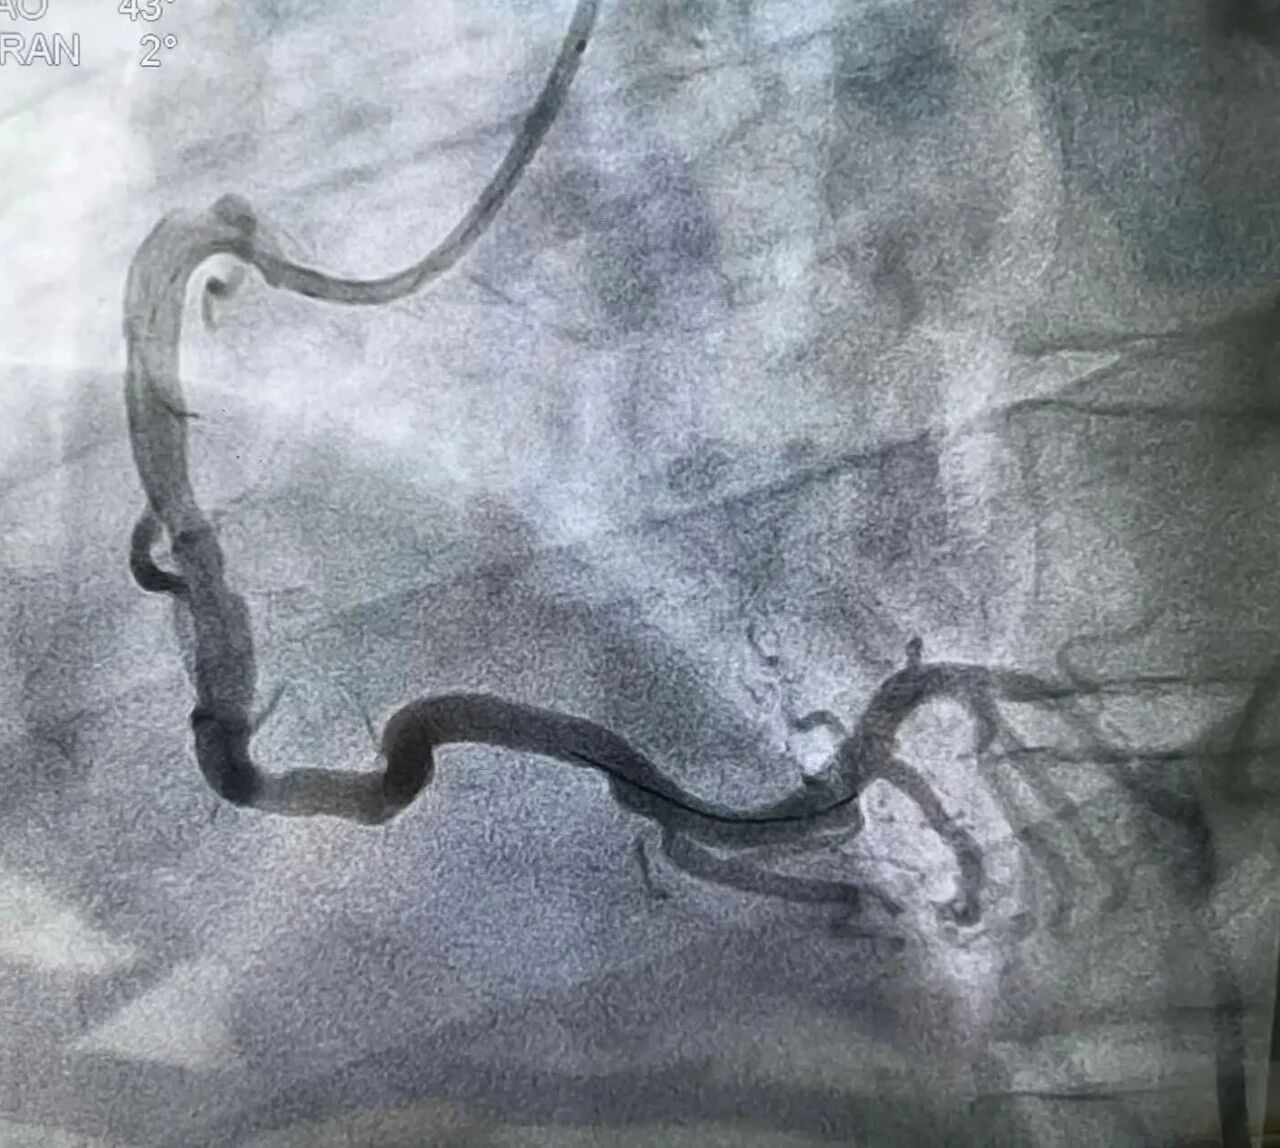

近日,一名34岁男性李某因突发胸痛1.5小时,被紧急送至周口人合医院急诊科。心电图提示“急性下壁心肌梗死”,情况危急!医院胸痛中心绿色通道立即激活,急诊冠脉造影显示右冠中段次全闭塞。医护团队迅速行动,快速开通闭塞血管并实施药物球囊扩张成形术,D2W(入门至导丝通过)时间仅31分钟,远低于国际标准90分钟!术后患者恢复良好,现已转危为安。

快速开通闭塞血管并实施药物球囊扩张成形术

术后